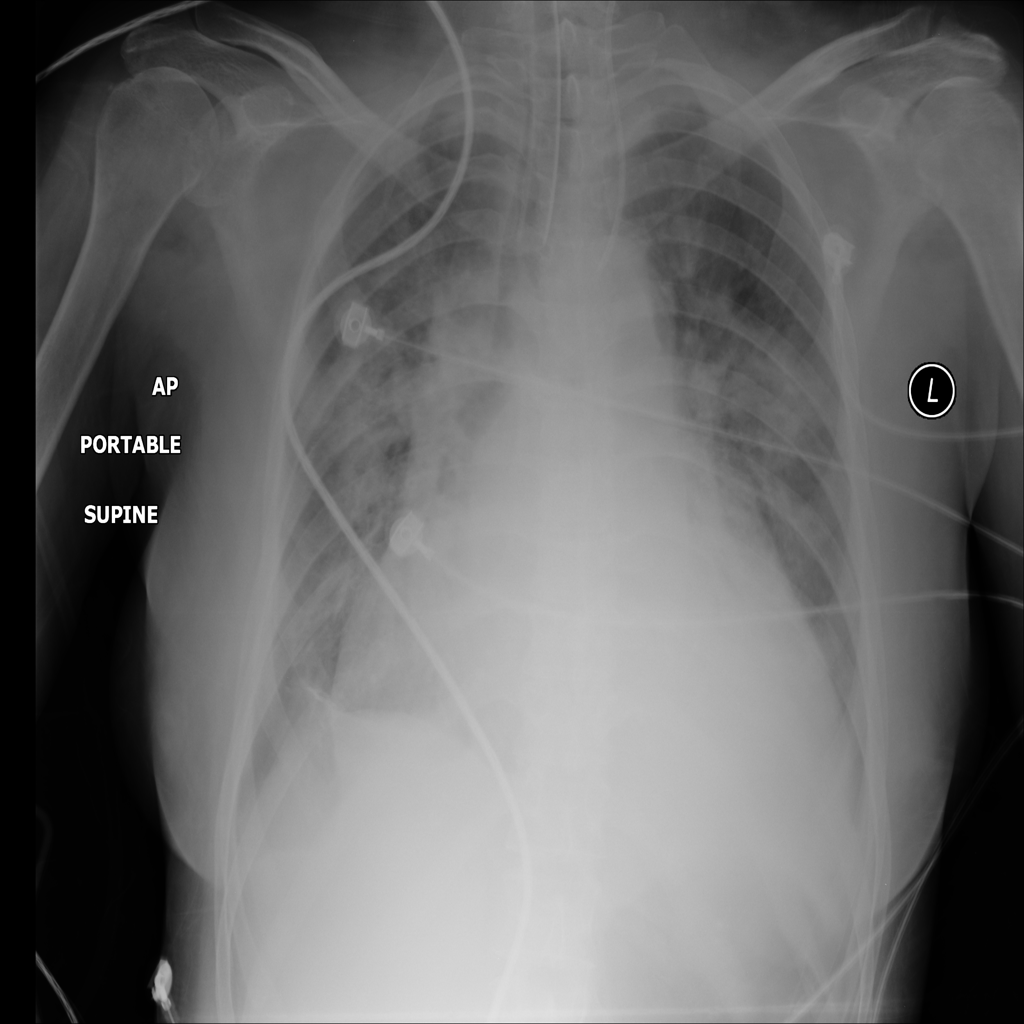

PAT-F3E7 · IMG-000Cardiomegaly

PAT-F3E7 · IMG-000

PA